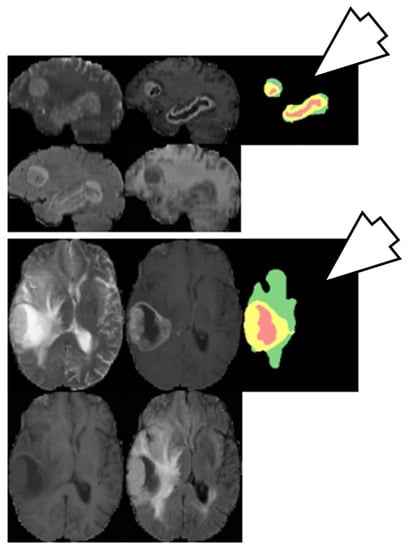

6.3.1. DL-Based Inter-Institutional Brain Tumor Segmentation

6.3.2. Brain Tumor Segmentation Using Two-Pathway CNN